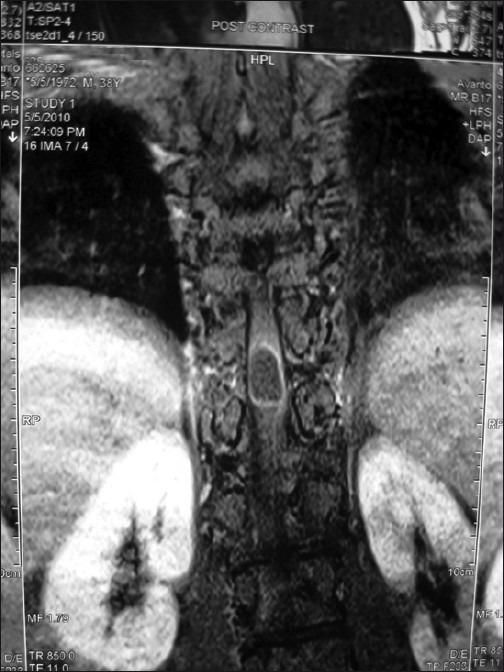

We report a case of intradural, intramedullary, spinal cord neurocysticercosis at dorsal 10-11 (D10-11) level in a mentally retarded male. A 38-year-old, mentally retarded male presented with weakness and stiffness in both the lower limbs and waist since one year. Magnetic resonance imaging revealed a D10-D11 intradural space occupying lesion with cord compression. Intraoperatively, the tumor was grayish white, soft, cystic, and intramedullary with a well-defined plane with surrounding cord tissue. Gross examination revealed a cystic lesion of 1.5×1×0.8 cm, with a whitish nodule of 0.3 cm in diameter. The cyst wall was thin, shiny, and translucent. Microscopic examination revealed cysticercous cyst. Spinal neurocysticercosis should be considered in differential diagnosis of spinal mass lesion in patients residing in endemic area such as India.

我们报告一例患有脊髓神经囊尾蚴病的智力迟钝男性病例,病变位于胸10 - 11(D10 - 11)水平的硬膜内、髓内。一名38岁智力迟钝男性,自一年前起出现双下肢及腰部无力和僵硬症状。磁共振成像显示在D10 - D11水平有一个硬膜内占位性病变并压迫脊髓。手术中,肿瘤呈灰白色、质软、囊性,位于髓内,与周围脊髓组织界限清晰。大体检查发现一个1.5×1×0.8厘米的囊性病变,伴有一个直径0.3厘米的白色小结节。囊肿壁薄、有光泽且半透明。显微镜检查显示为囊尾蚴囊肿。对于居住在印度等流行地区的患者,在对脊髓肿块病变进行鉴别诊断时应考虑脊髓神经囊尾蚴病。